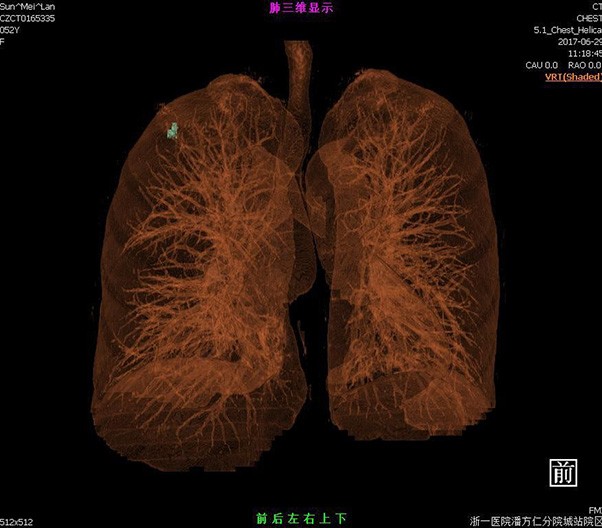

Lung reverse scanning eliminate respiratory motion artifact

NDI NanoDose Iteration Algorithm (NDI) is an innovative iterative technique for image reconstruction that takes full advantage of deep learning in anatomical structure in image space as well as model-driven iteration involving tube and detector in projection space, with the aim to generate sharp and high-resolution images at the lowest possible dose.

臨床畫廊